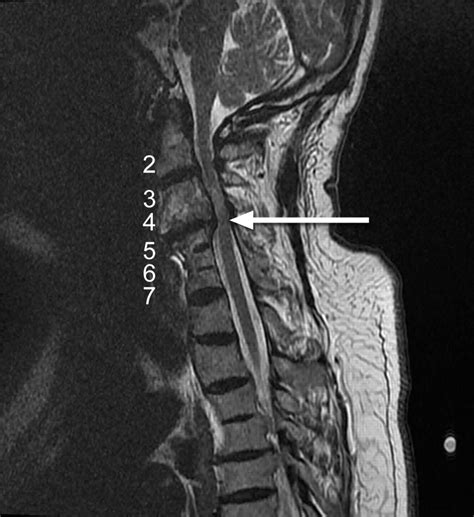

• Imaging Studies: Various imaging techniques are used to visualize the spine and identify the presence of osteophytes. These may include:

MRI Provides detailed images of the soft tissues, including the intervertebral discs and spinal nerves, and can help assess the extent of nerve compression.